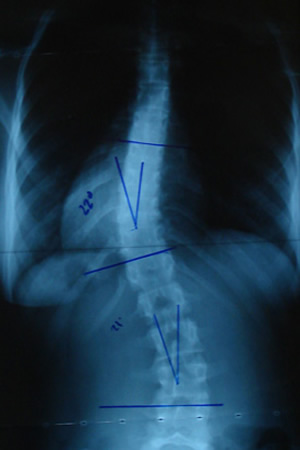

Grafilerle Skolyoz